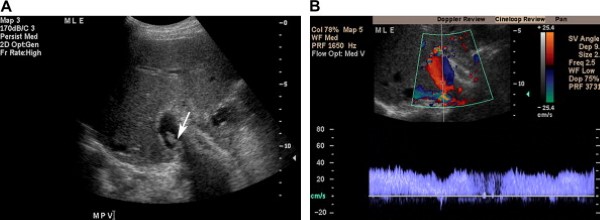

Tĩnh mạch cửa được tạo thành do hợp nhất tĩnh mạch lách với tĩnh mạch mạc treo tràng trên và mang máu từ ruột, tụy, lách tới gan (Hình 1). Các ngành phải và trái của nó tách ra ở cửa gan, sát với động mạch gan và ống gan chung. Tĩnh mạch cửa và các nhánh trong gan có thành mỏng, hơi tăng âm, và dòng chảy trong hệ thống tĩnh mạch cửa luôn hướng vào gan. Với các mặt cắt liên sườn hoặc dưới sườn, dòng máu trong tĩnh mạch cửa và ngành trái hướng tới đầu dò, và dòng chảy ở ngành phải đi xa đầu dò.

Phổ Doppler biểu hiện sóng một pha hầu như không biến đổi theo hô hấp (Hình 2). Tốc độ trung bình trong tĩnh mạch cửa từ 13 tới 23 cm/s khi nhịn đói [2].

Hình 2. Tĩnh mạch cửa bình thường ở bệnh nhân nam 48 tuổi có tiền sử HIV và xuất huyết tiêu hóa thấp. (Hình A) Ảnh thang xám cho thấy tĩnh mạch cửa bình thường chia thành ngành phải và trái đi vào gan, tĩnh mạch có thành tăng âm và trong lòng mạch có các chấm đậm âm nhỏ. (Hình B) Ảnh siêu âm duplex Doppler và màu cho thấy dòng chảy tĩnh mạch cửa về gan với sóng tĩnh mạch dạng một thì (pha) thay đổi rất ít theo hô hấp. Dòng máu trong tĩnh mạch cửa và ngành trái hướng tới đầu dò (màu đỏ). Ở ngành phải tĩnh mạch cửa, dòng máu chảy xa đầu dò (màu xanh). Tốc độ trung bình 35 cm/s. Lưu ý bệnh nhân có nhiều dịch ổ bụng.